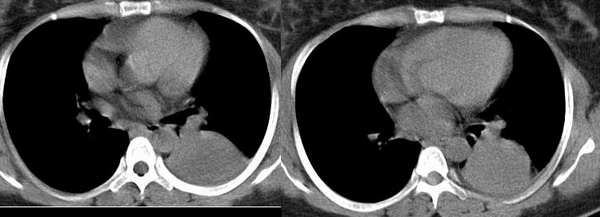

以下是引用wawaquan在2006-2-4 13:32:00的发言:[br]双上叶后段及右下叶多发大小不等圆形高密度影,与血管影相连;左下叶背段呈软组织密度影,边缘膨突,其内见一点状气体密度影,邻近胸膜增厚;纵隔淋巴结不大。[br] 女性,32岁,正哺乳期。近一周发热咳嗽,今晨咳血一次。 [br] 考虑:①双上叶后段及右下叶多发转移瘤,建议查盆腔排除子宫滋养叶细胞肿瘤。[br]②左下叶背段阻塞性炎症可能大。